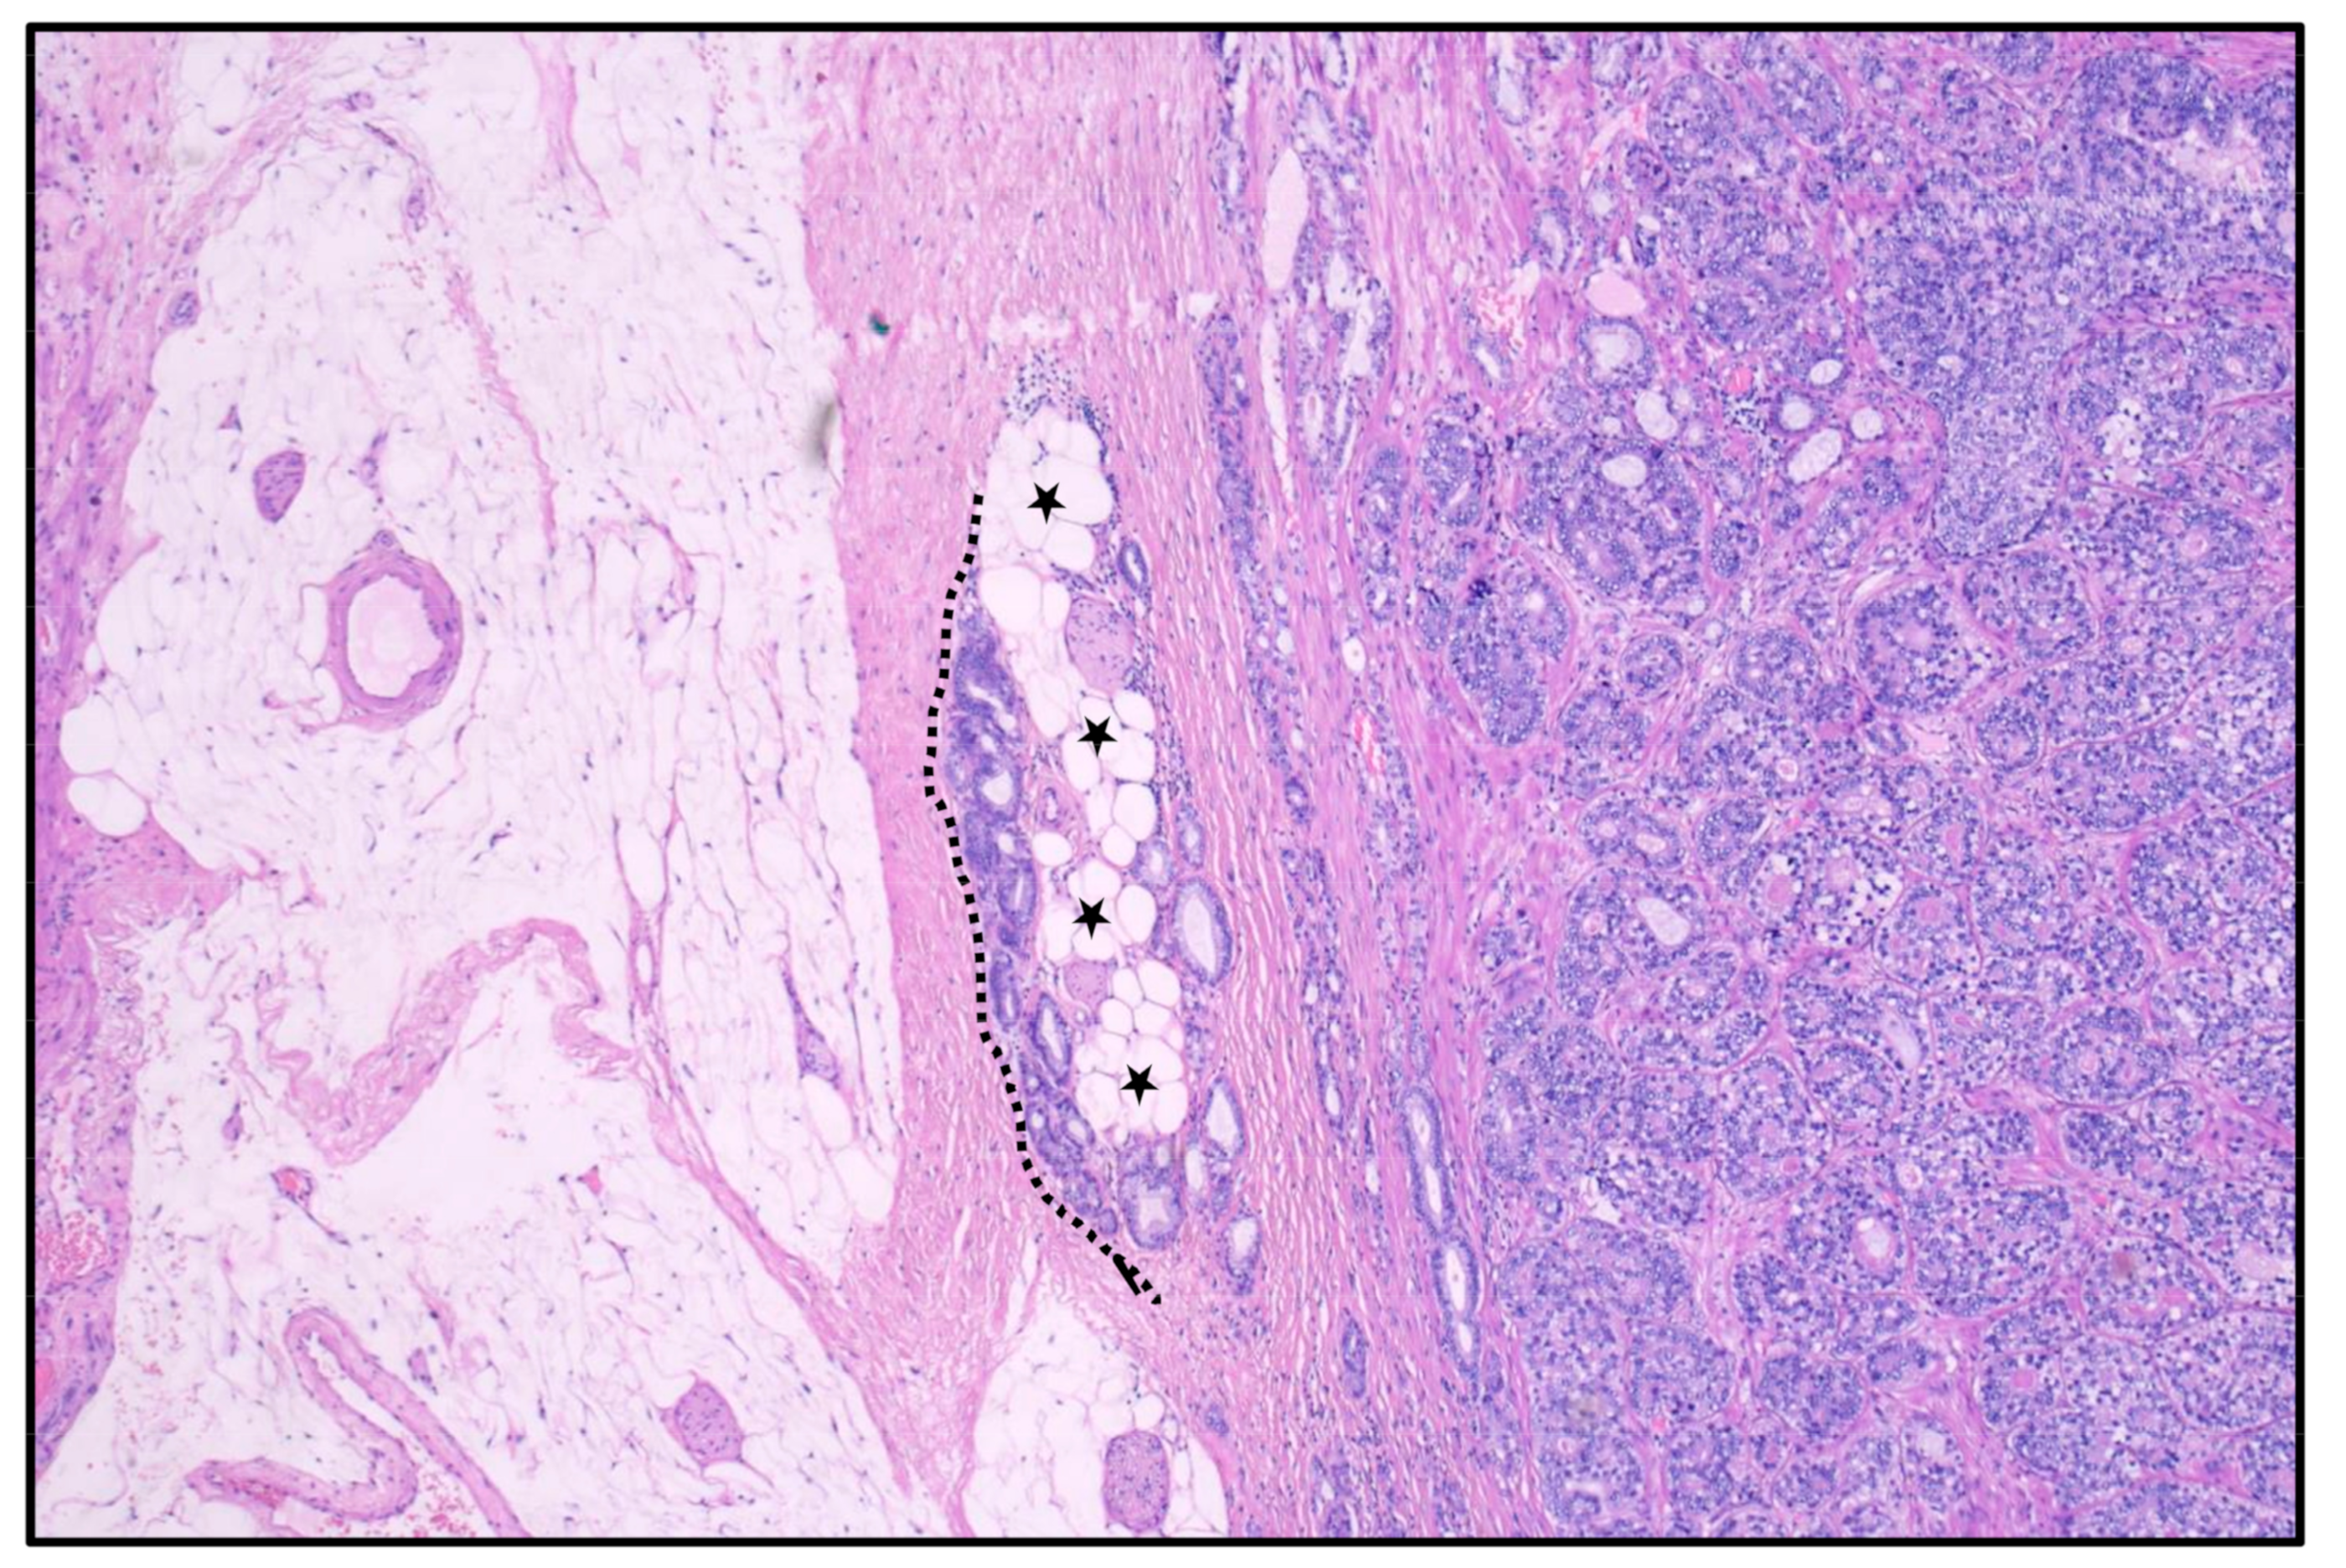

5. The Lateral and Dorsal Surface with Seminal Vesicles

6. Extraprostatic Growth and Oncological Implications